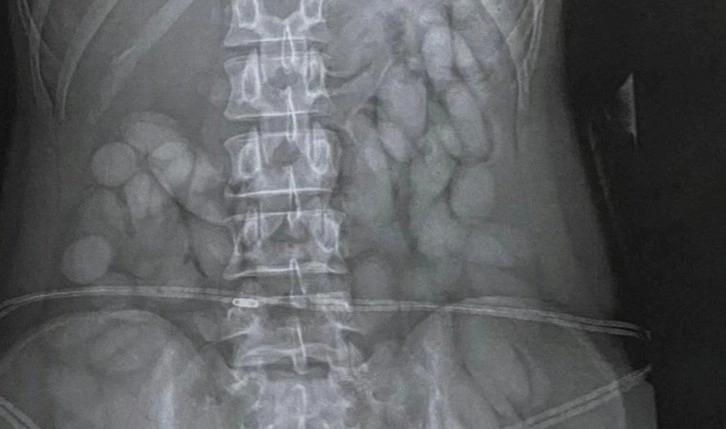

Tutuklanmasının ardından yerel bir hastaneye götürülen kadının çekilen röntgeninde midesinde yuttuğu anlaşılan cisimler tespit edildi.

Güney Afrika polisi, kadının polis koruması altında, toplam ağırlığı yaklaşık 850 gram olan 68 adet kokain şüphesi taşıyan “cisim” bıraktığını söyledi.

Fotoğraf: Kadının midesinden çıkarılan kokain yüklü cisimler